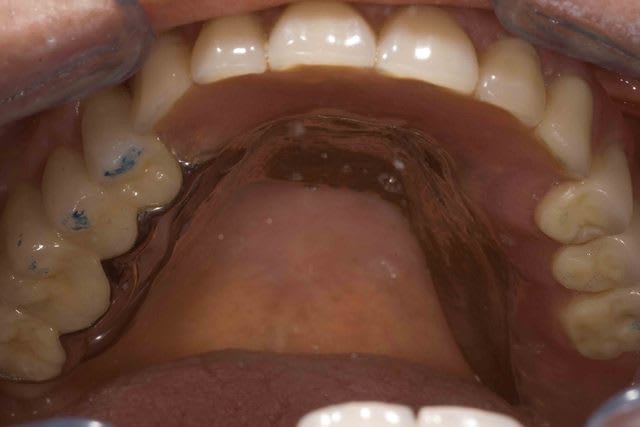

Tant qu'on y est a poster des cas foireux j'ai celui la fini il y a 6 mois.

La patiente sors de son dentiste et viens directement chez moi :

1° Pap maxillaire qui ne tient pas . Effondrement de l'étage moyen de la face avec propulsion mandibulaire pour rechercher une proprioception antérieure .

2° La PAP mandibulaire impossible a mettre en place tellement elle est douloureuse.

3° Pour le sourire je vous fait pas de dessin, il suffit de regarder les photos.